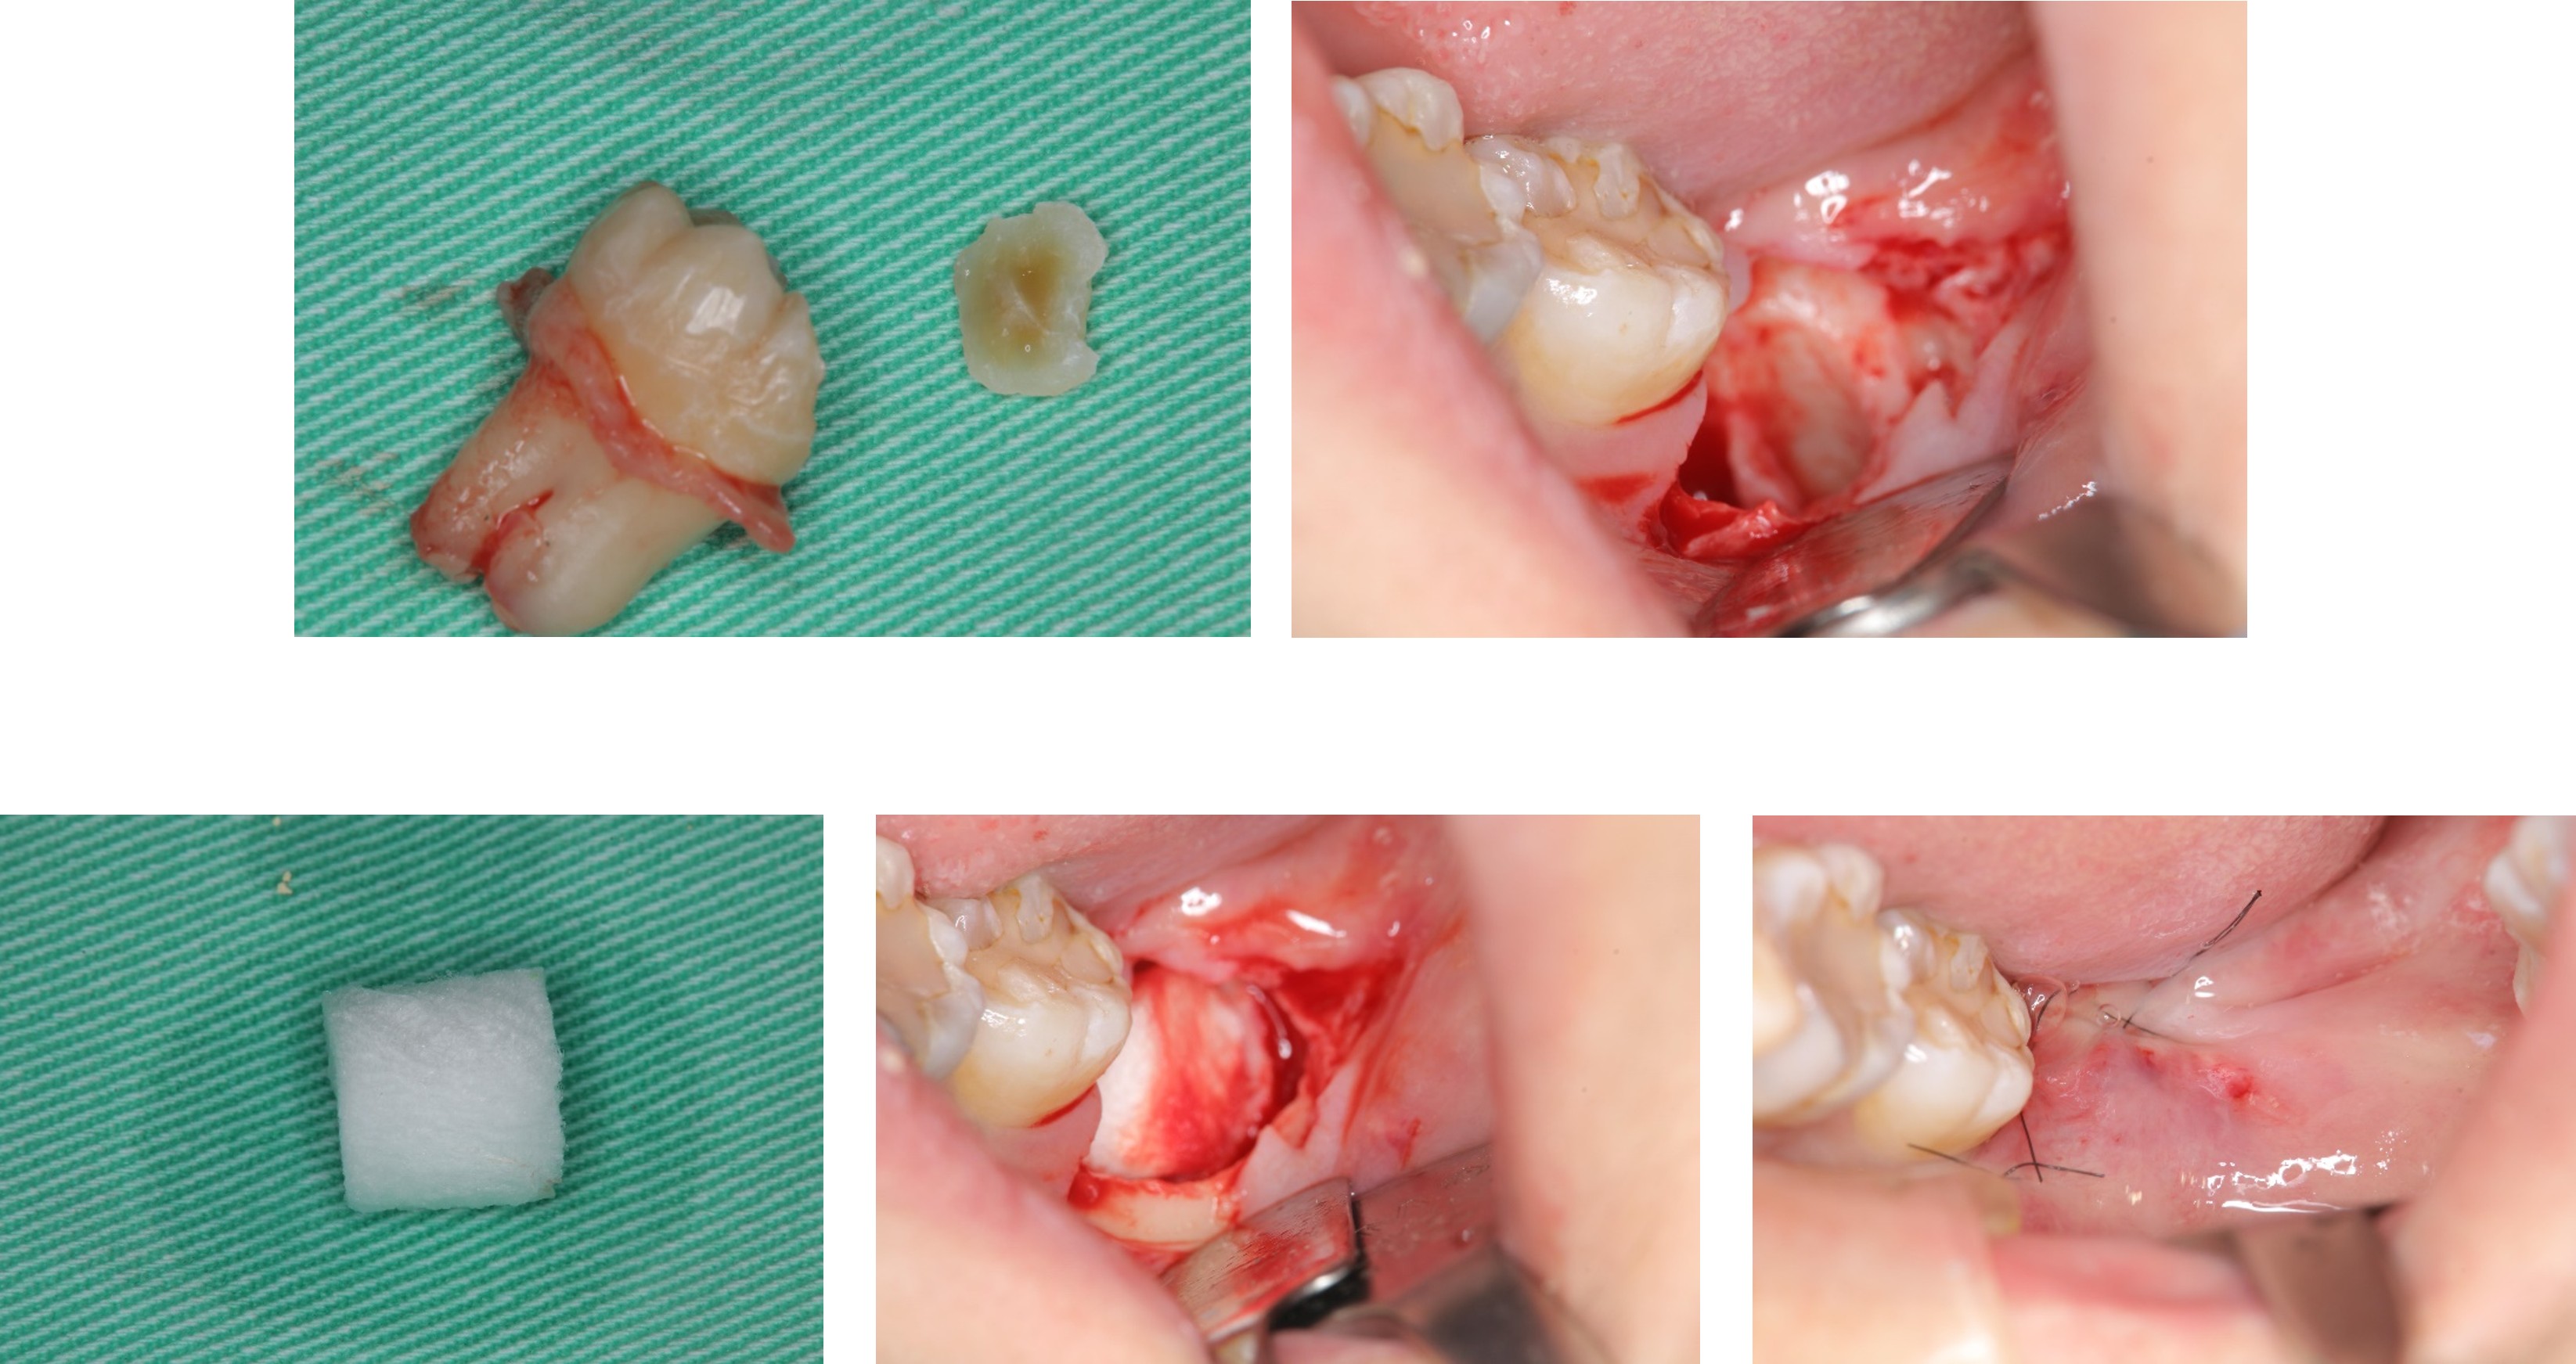

拔牙,並以骨膠原修復

以骨膠原修復,並縫合之